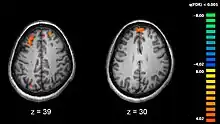

Recent research using neuro-imaging technology including PET and fMRI scanning has shown that there is an extensive amount of distributed brain activation during the process of episodic encoding and retrieval. Among the various regions, the two most active areas during the constructive processes are the medial temporal lobe (including the hippocampus) and the prefrontal cortex.[15] The Medial Temporal lobe is especially vital for encoding novel events in episodic networks, with the Hippocampus acting as one of the central locations that acts to both combine and later separate the various features of an event.[16][17] Most popular research holds that the Hippocampus becomes less important in long term memory functioning after more extensive consolidation of the distinct features present at the time of episode encoding has occurred. In this way long term episodic functioning moves away from the CA3 region of the Hippocampal formation into the neocortex, effectively freeing up the CA3 area for more initial processing.[17] Studies have also consistently linked the activity of the Prefrontal Cortex, especially that which occurs in the right hemisphere, to the process of retrieval.[18] The Prefrontal cortex appears to be utilized for executive functioning primarily for directing the focus of attention during retrieval processing, as well as for setting the appropriate criterion required to find the desired target memory.[15]